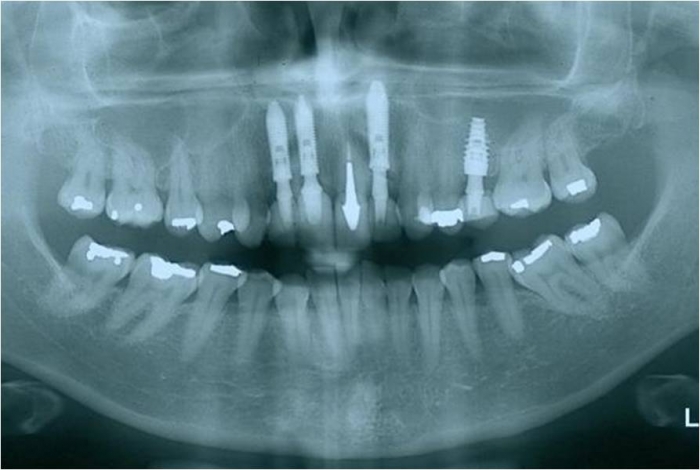

Rx após extração e implantes imediatos nos dentes 12 e 22

Raio X final